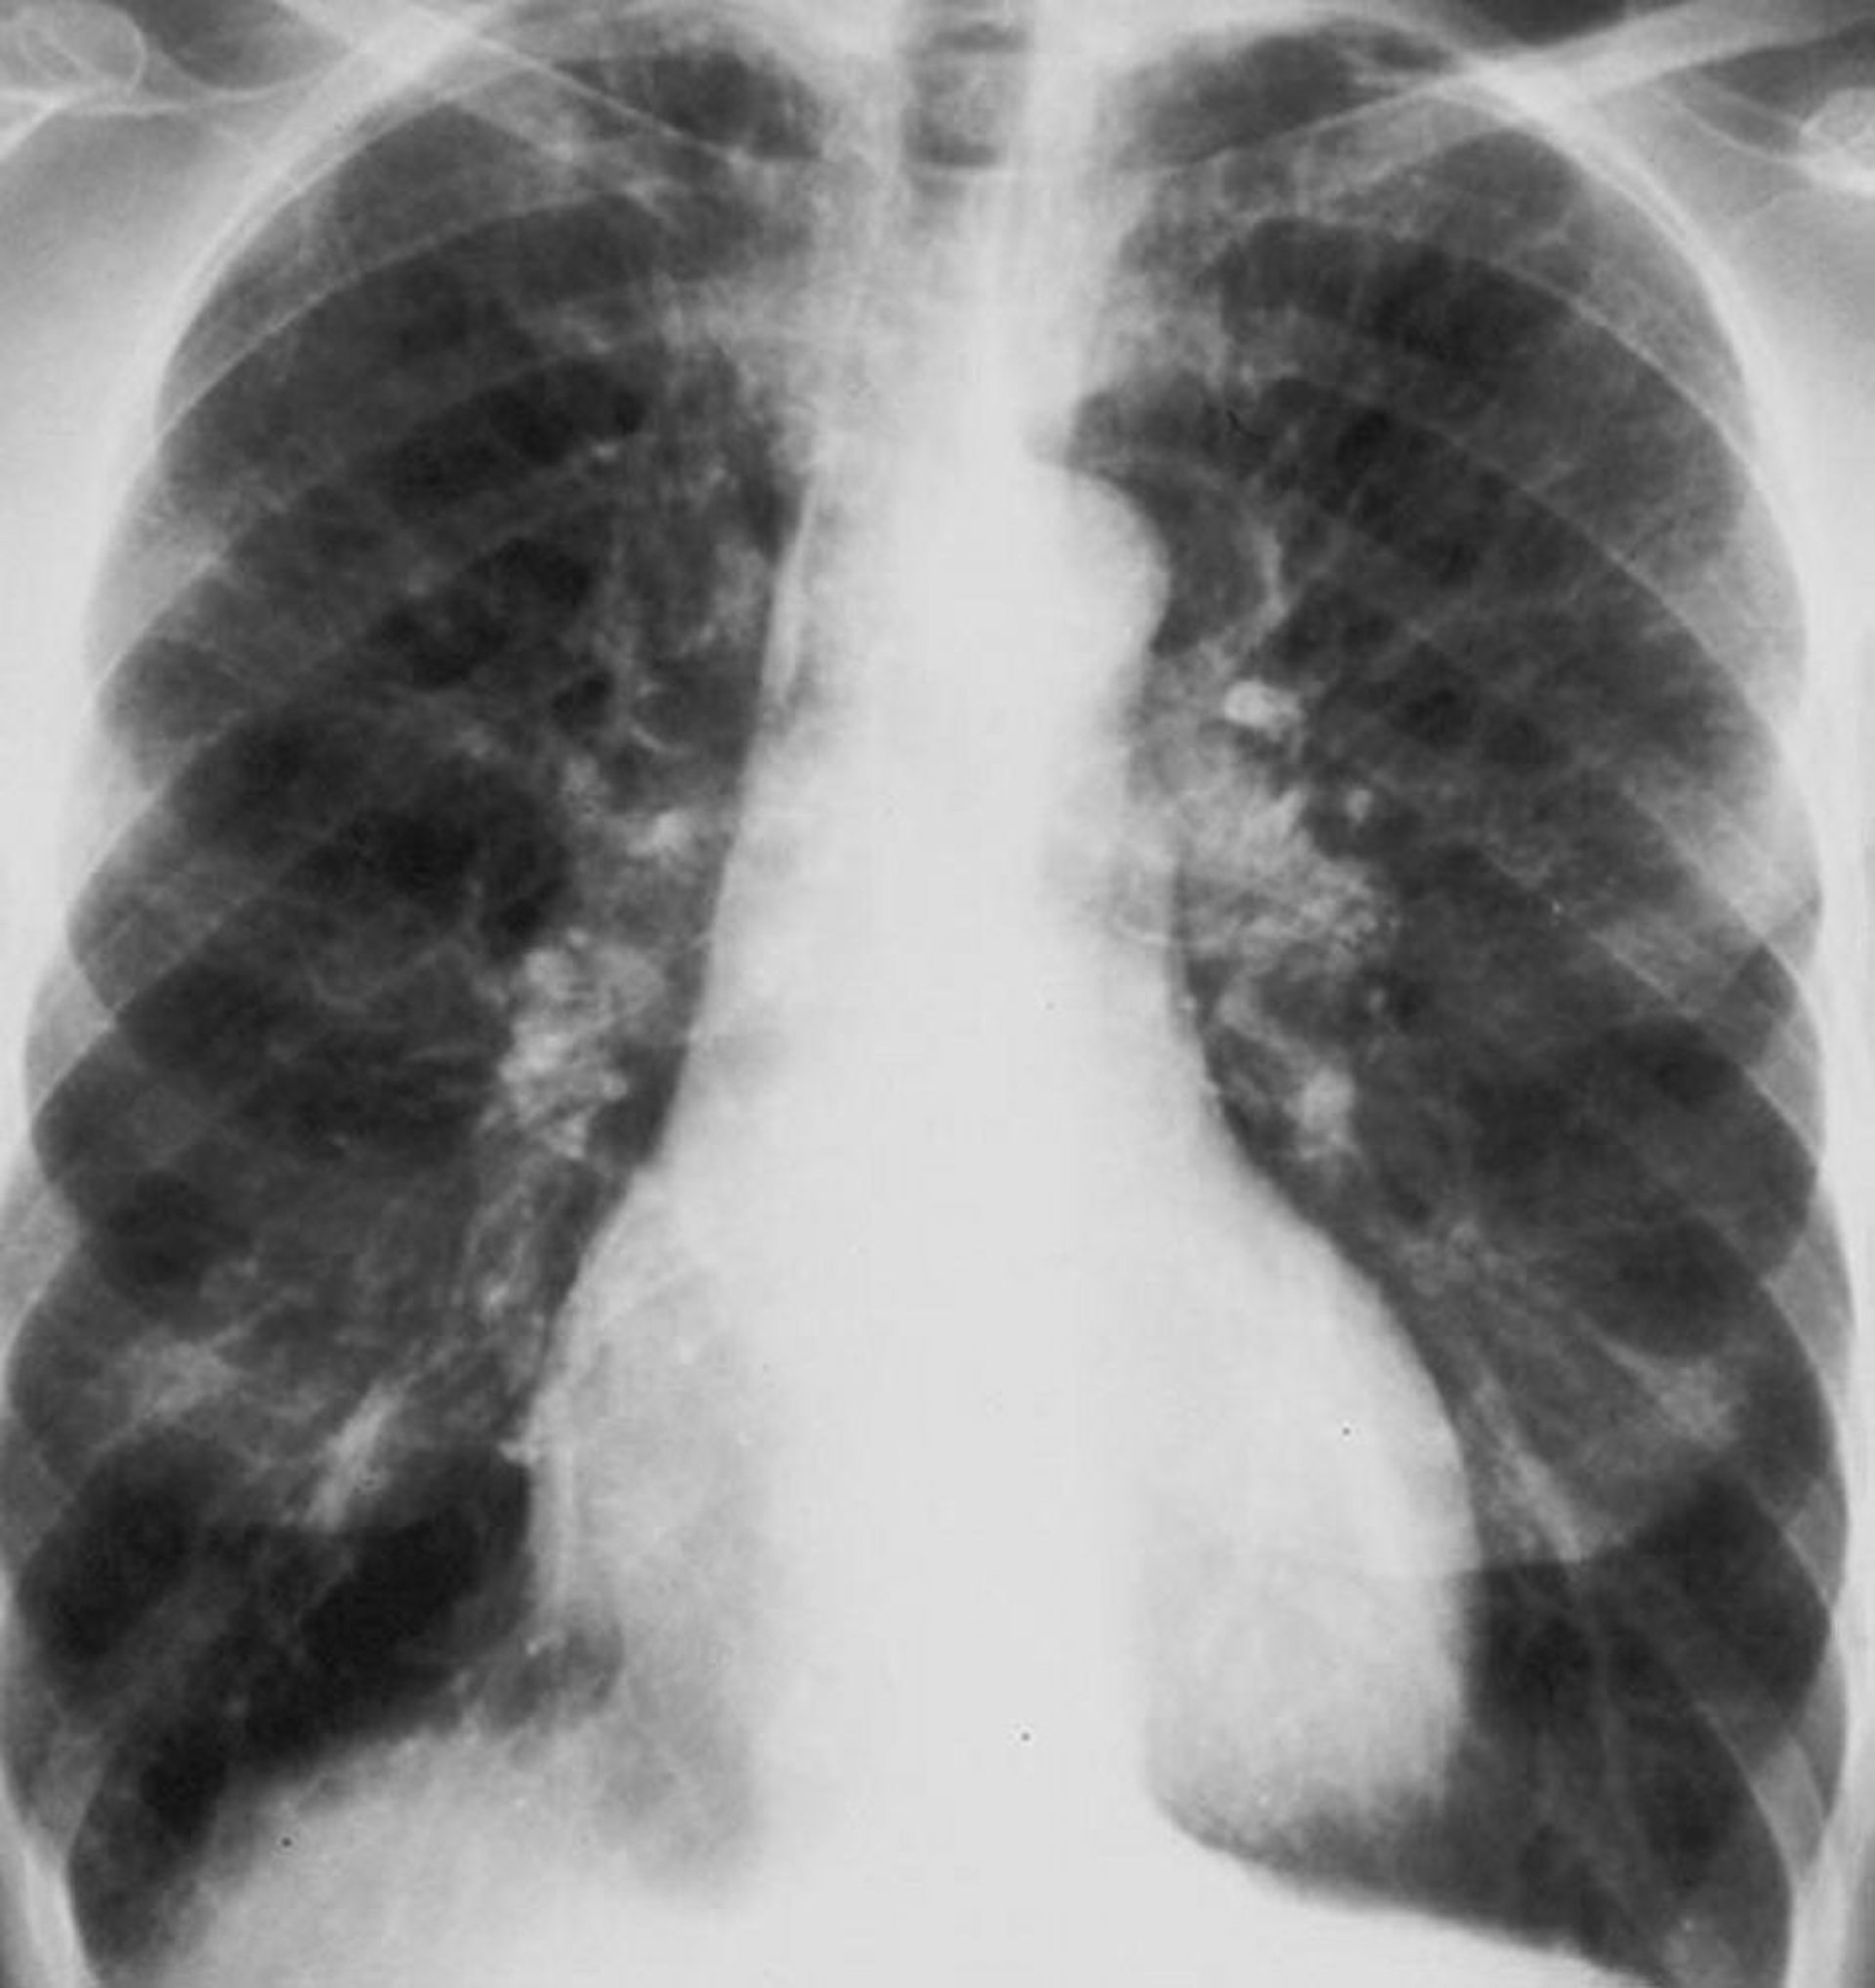

Chronic Obstructive Pulmonary Disease (Chest Radiograph)

Chest radiograph of a patient with chronic obstructive pulmonary disease (COPD). The lungs are hyperinflated, the diaphragm is flattened, vascular markings are increased, and the heart size is marginally increased.